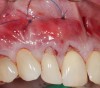

Fig 7. APRF membrane placement. A “distal-mesial backpack” technique ensures a dense and complete packing of the APRF membranes in the pouch created. Three to 4 membranes are recommended per pair of teeth treated.

Figure 7

Fig 8. Apical periosteal suture below the mucogingival junction will “lift” the APRF/flap complex coronally. This intimate proximity of the APRF membranes with the periodontal ligaments will allow for a slow release of growth factors, thus promote keratinization.

Figure 8